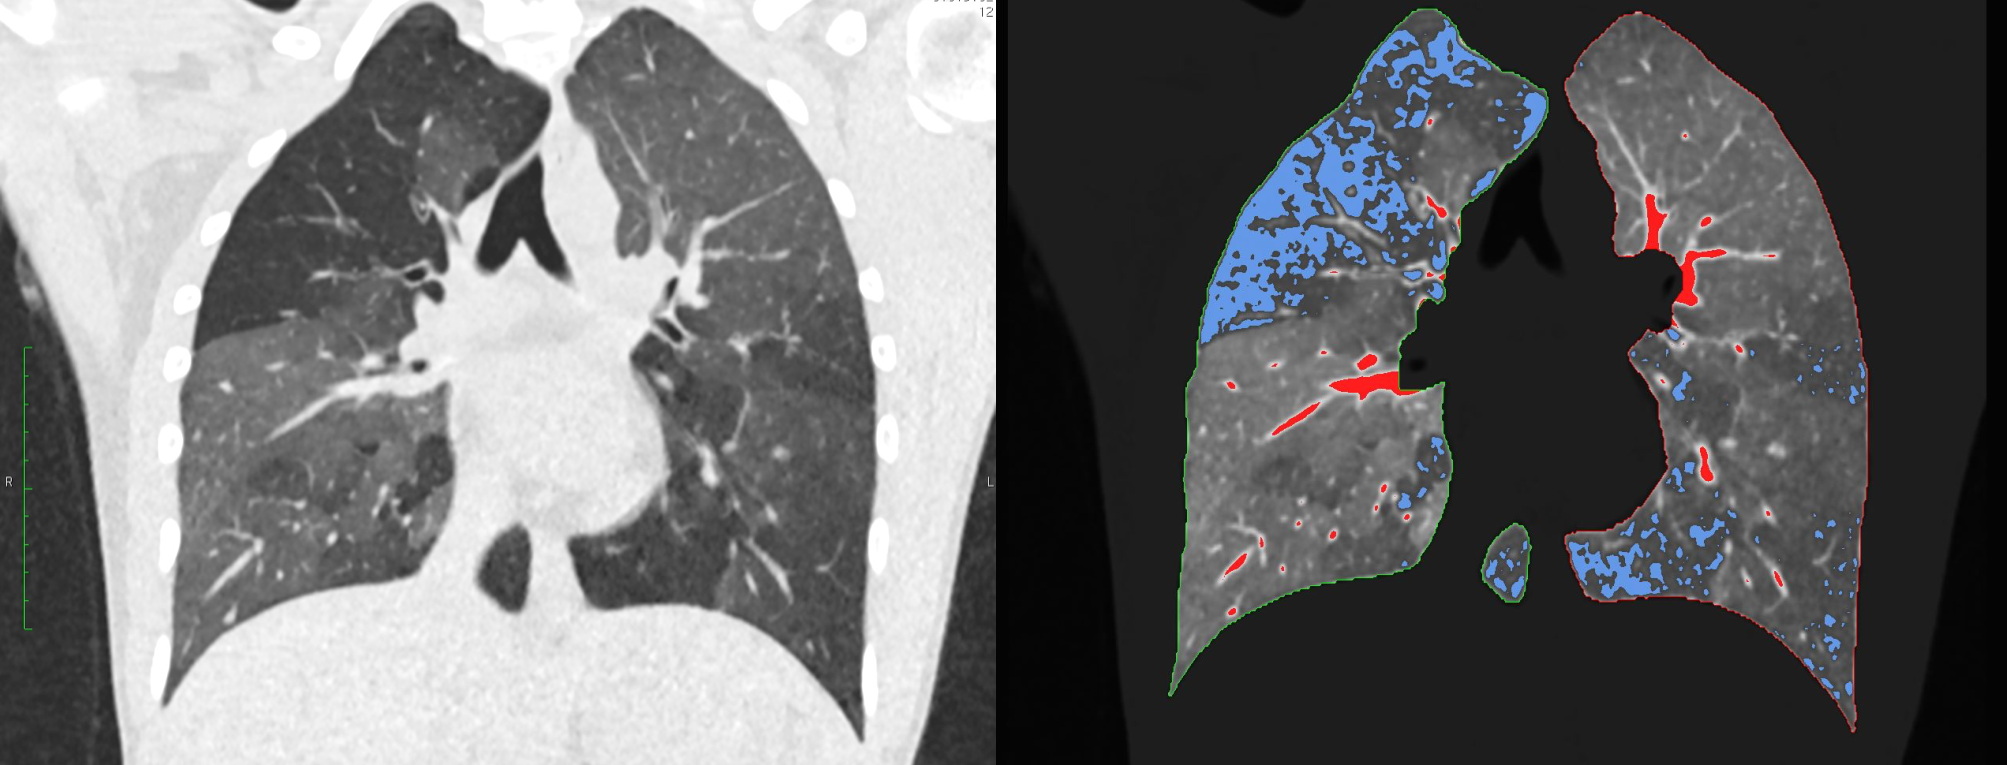

Mit den umfangreichen Datensätzen moderner CT-Geräte lassen sich in Zeiten, in denen Computerkapazitäten kaum ein Problem mehr darstellen, aber auch ganz andere Auswertungen machen. Ein Beispiel ist die quantitative Computertomographie (qCT). „Bei diesem Verfahren wertet die Software nicht nur durchschnittliche Dichtewerte aus, sondern analysiert jeden einzelnen dreidimensionalen Pixel oder ‚Voxel‘ separat und setzt sie miteinander in Verbindung“, erläutert Gawlitza.

In einem Organ wie der Lunge kann das hoch interessant sein: Dort wertet die qCT pro Lungenflügel mehr als zwei Millionen Voxel aus. Bei Patienten mit einer chronisch-obstruktiven Lungenerkrankung (COPD) zum Beispiel ist die Lunge nicht homogen belüftet. Es gibt vielmehr Areale, in denen die Luft beim Ausatmen „steckenbleibt“ und andere, die weitgehend normal arbeiten. „Solche schlecht belüfteten Areale können wir mit der qCT erkennen“, so Gawlitza. Ein anderes Beispiel sind Verkalkungen der Herzkranzgefäße, die in der normalen CT ohne Quantifizierung lediglich als dichte Ablagerungen erscheinen. In der qCT dagegen kann der Aufbau der Kalk-Plaques sowie deren Volumen detailliert dargestellt und vor allem quantifiziert werden. Insbesondere für die individuelle Risikoabschätzung des Patienten ist dies relevant.

Konkret haben die Mannheimer mehrere qCT-Parameter – darunter Lungenvolumen, mittlere Lungendichte und den Anteil der schlecht belüfteten Lungenareale – in ein neuronales Netzwerk gefüttert. Zum Einsatz kam das dafür in Mannheim eigens für die qCT-Auswertung der Lunge entwickelte Programm PrediCT. „Letztlich rechnet die Software die Lungenfunktion auf Basis unterschiedlicher Modelle durch und bildet einen Mittelwert. Den haben wir dann mit dem Goldstandard, einer Messung der Lungenfunktion mittels Bodyplethysmographie, verglichen“, so Gawlitza.